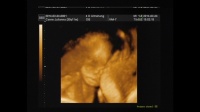

Kislányom a 4d-s ultrahangon....